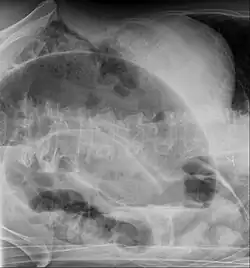

CT scan of a small bowel volvulus. It shows two juxtaposed segments of narrowing, which is the spot of mesentery rotation. The other signs indicate strangulation. -

An x-ray of a person with a small bowel volvulus.